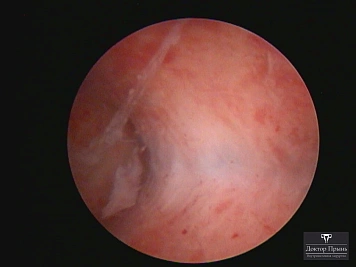

Как правило, синехии находят при УЗИ. Когда по УЗИ патологии нет, а симптомы есть, выполняют гистероскопию – это золотой стандарт в определении синехий.

Гистероскопия позволяет не только увидеть спайки, но и сразу вылечить, т.е. рассечь их. Большинству пациенток подойдёт офисная гистероскопия без наркоза и госпитализации. Среднее время операции 15 минут. Иногда требуется 2-4 операции, чтобы восстановить полость матки.

Крайне важен способ разделения спаек. Если это холодный инструмент, например, ножницы, то вероятность рецидива низкая. Плюс не повреждается нормальный эндометрий. Если рассекают горячей электропетлёй, то, наоборот, риск рецидива высокий и можно обжечь эндометрий.

Синехии, рассечённые Прынь Д.В.